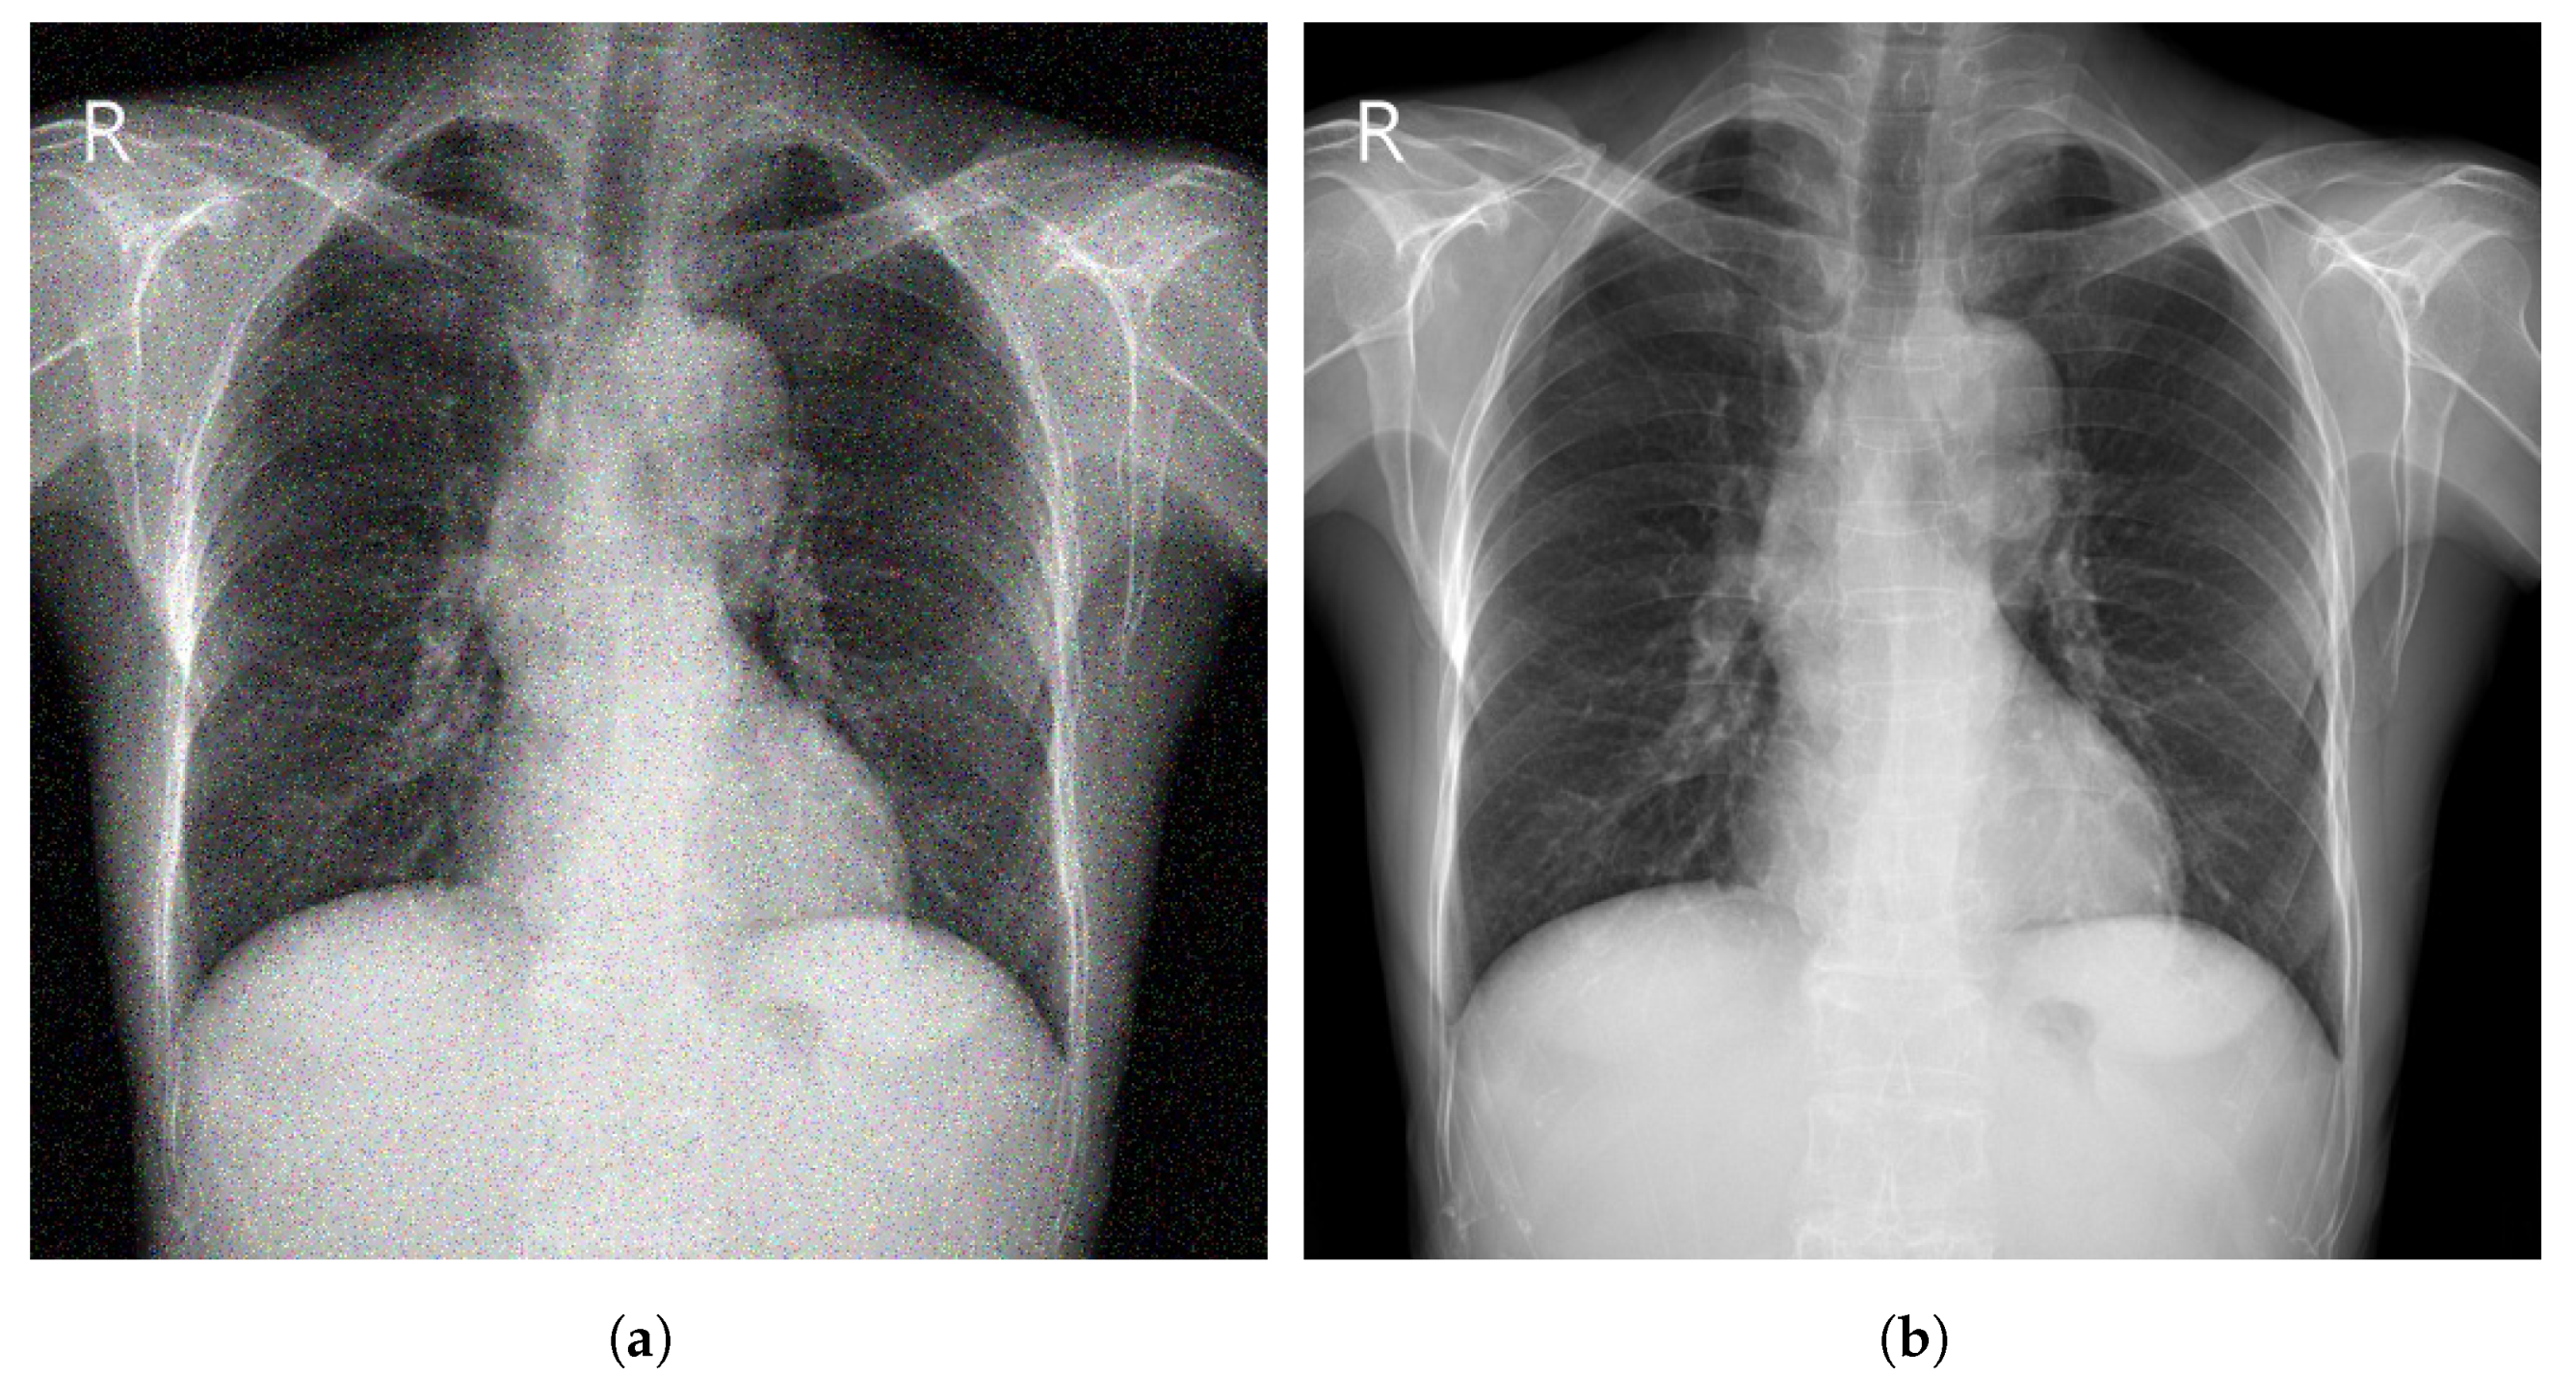

Image enhancement techniques are generally used to improve the information interpretability in images. For CXR images, these techniques are used to provide a better image quality to human readers (radiologists) as well as to automated systems [71]. To improve the quality of a CXR image, multiple parameters can be considered (contrast, brightness, noise suppression, edge of features, and sharpness of edges) using different methods including histogram equalization (HE) [72], high and low pass filtering [73], and unsharp masking [74]. Figure 5 depicts an example of enhancement applied to a CXR image.

Figure 5.

(a) Noisy CXR image from a low quality version of CheXpert dataset [44]; (b) Enhanced CXR image.